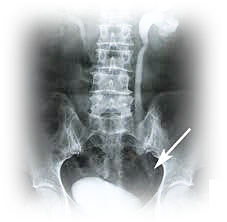

이러한 결석은 보통 신장에서 발생합니다.

신장, 요도, 방광, 요도 등에 있습니다

문제를 일으키고 있어요.